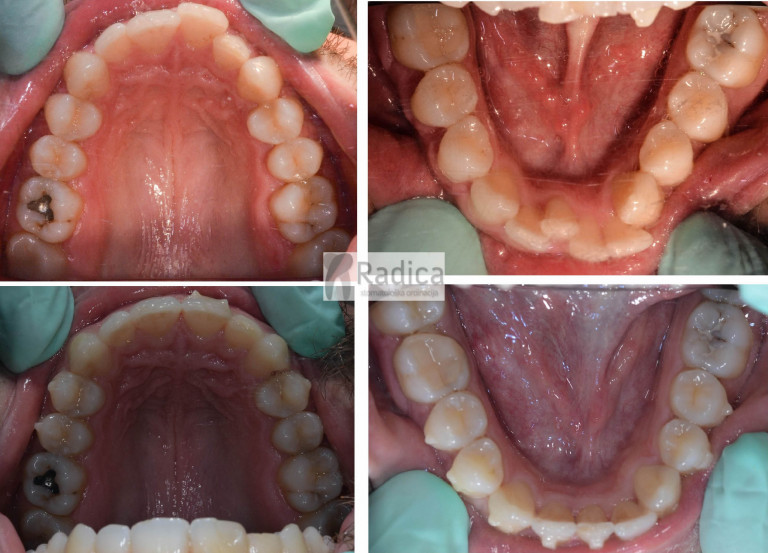

Slučaj 1: ispravljanje otvorenog zagriza i kompresije Invisalign full terapijom

Slučaj 2: ispravljanje kompresije Invisalign full terapijom- u ovom slučaju je izvađen jedan donji sjekutić

Slučaj 3: ispravljanje kompresije Invisalign full terapijom

Slučaj 4: ispravljanje kompresije Invisalign full terapijom